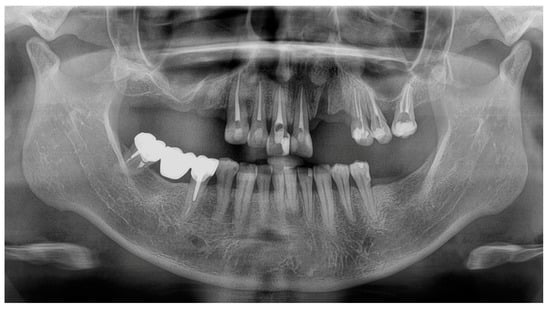

At a 2-year follow-up, the patient was completely satisfied with the rehabilitation and expressed no complaints (Figure 8). The maxillary RPD clasps were slightly retightened on teeth #25 and #26, and standard periodontal maintenance was carried out.

Figure 8. Follow-up at 2 years: (A) smile view; (B,C) occlusal views of maxillary and mandibular definitive prostheses; and (D) panoramic radiography.